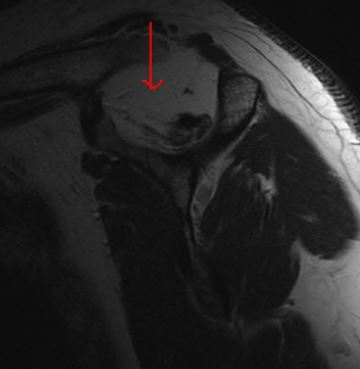

Fatty Infiltration of Supraspinatus